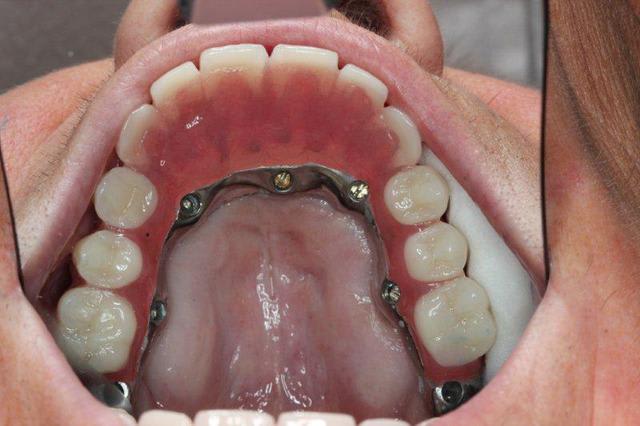

> j'aimerais éventuellement voir une photo de ta barre au lingual

Oui je vois le patients en janvier je te fais ça

Les plaques existent depuis environ une dizaine d années

Je suis un des tous premiers à en avoir posé en dehors de GS puisqu à l époque il m en a confié une pour poser à la mandibule chez une patiente où je n avais pas pu poser un monodisk

J ai posé cette plaque en quais totalement enfoui à l époque : elle tjs là totalement indolore, bien sonore comme un cylindre

Je vais te filer qques photos d une patiente opérée voici 3 ans avec du nano et des plaques rien que l aspect de la muqueuse te montrera que tout ça est sain et ossifié

Img 1182 s6mmza - Eugenol

Img 1193 e1whny - Eugenol

Img 1194 xpaov4 - Eugenol